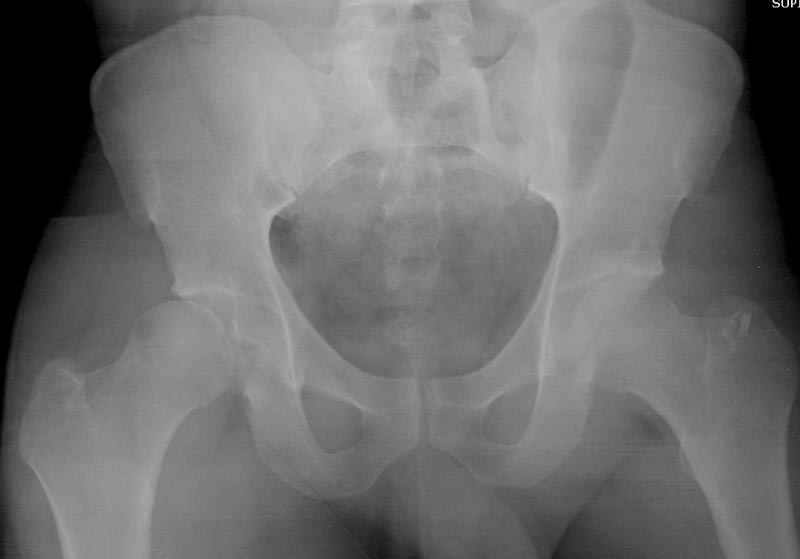

5:24 Рентгенограмма таза, вызывают врача ортопеда (снимок N1), его диагноз: закрытый переломо-вывих правого тазабедренного сустава, получает добро на закрытую репозицию в приемном отделении

5:38 Дважды неудачная попытка закрытой репозиции в приемном отделении